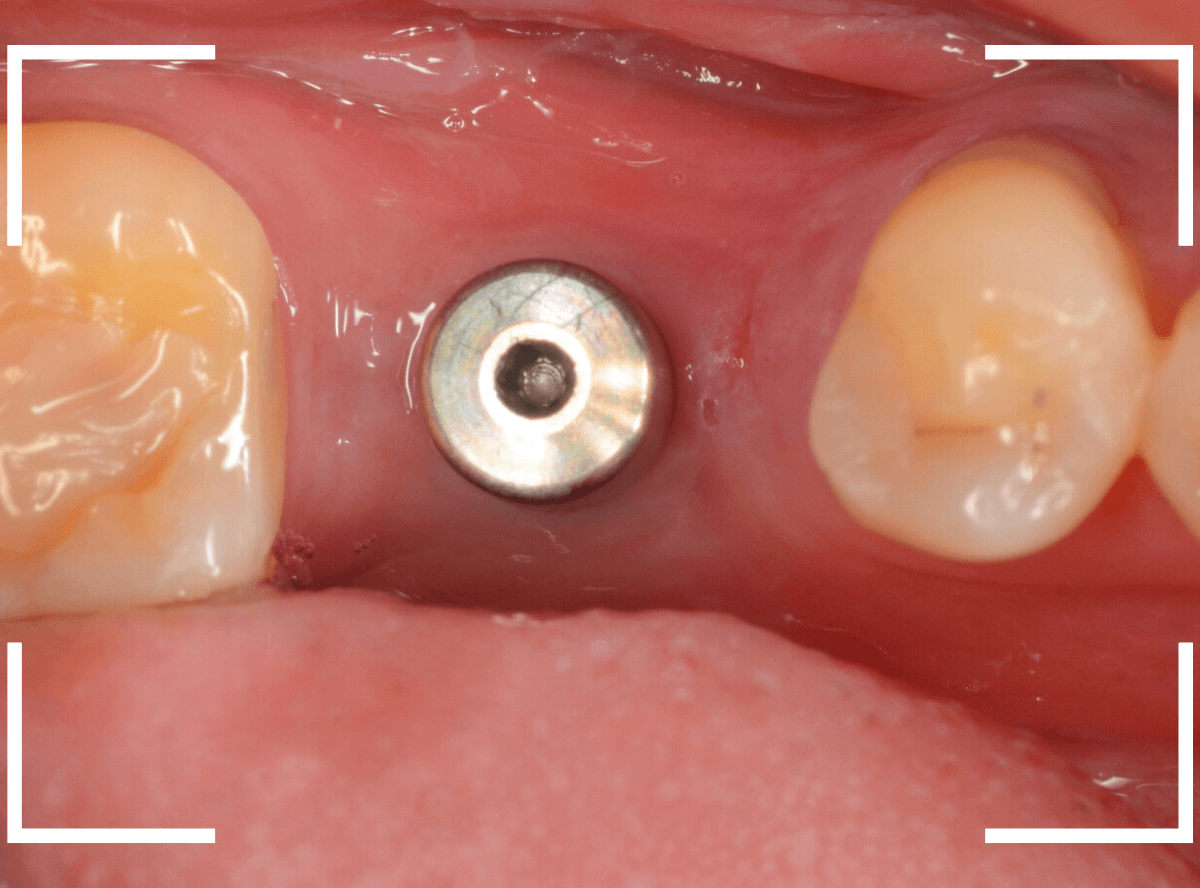

奥歯のインプラント治療例

下の奥歯にインプラントを埋入した方の例です。

インプラント周囲の歯肉も問題なく改善しています。

よくたずねられるのですが、真ん中の穴はアクセスホールといい、インプラントの着脱の時に使用する、ネジ穴です。

set、調整が終われば、アクセスホールを埋めて、治療終了です。

何かあれば、アクセスホールを開けてインプラントを着脱できるようになっています。